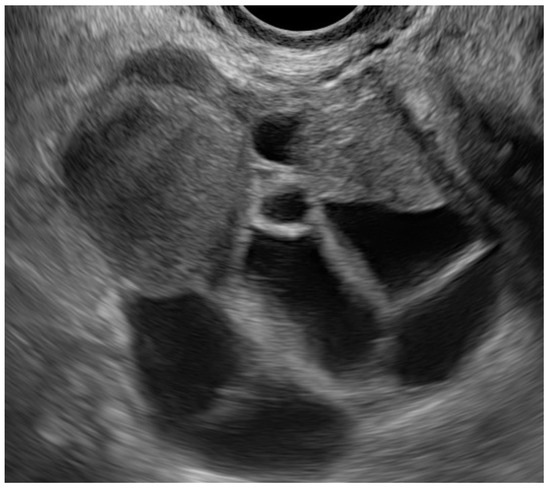

- Guerriero, S.; Condous, G.; van den Bosch, T.; Valentin, L.; Leone, F.P.G.; Van Schoubroeck, D.; Exacoustos, C.; Installé, A.J.F.; Martins, W.P.; Abrao, M.S.; et al. Systematic approach to sonographic evaluation of the pelvis in women with suspected endometriosis, including terms, definitions and measurements: A consensus opinion from the International Deep Endometriosis Analysis (IDEA) group. Ultrasound Obstet. Gynecol. 2016, 48, 318–332. [Google Scholar] [CrossRef] [PubMed]

- Guerriero, S.; Spiga, S.; Ajossa, S.; Peddes, C.; Perniciano, M.; Soggiu, B.; De Cecco, C.N.; Laghi, A.; Melis, G.B.; Saba, L. Role of imaging in the management of endometriosis. Minerva Ginecol. 2013, 65, 143–166. [Google Scholar] [PubMed]